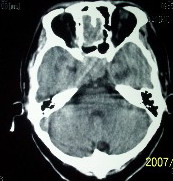

f    29岁   头闷  头晕1月余

肿瘤累及颅底前颅窝,部分层面见散在钙化,中心坏死。支持:脑膜瘤!

右额叶底部巨大等低混杂密度肿块,边界清楚,周围水肿轻度,明显占位效应。蝶鞍扩大,部分骨质破坏。

考虑脑膜瘤,建议增强扫描进一步检查。

蝶鞍受压吸收,可以排除室管膜瘤。肿瘤最大层面不在蝶鞍可以排除垂体瘤。支持脑膜瘤